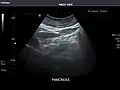

Pancreas -

Pancreas: Visualized portions unremarkable.